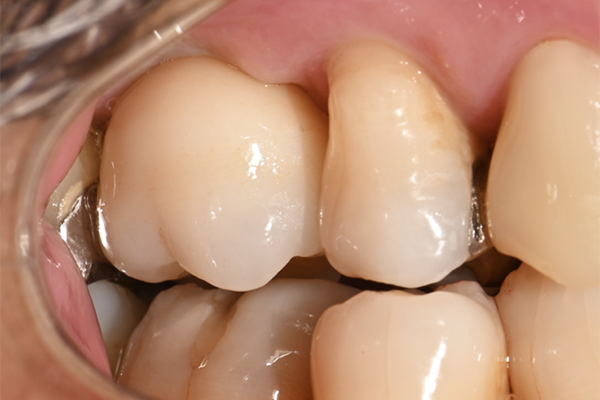

| 主訴 | 奥歯で噛めない、顎が痛い |

|---|---|

| 治療内容 | 奥歯のインプラント治療、前歯・奥歯の被せ物治療 |

| 治療期間 | 6ヶ月 |

| 治療費 | 350万円 |

| 治療リスク | 被せ物をつけた初期の段階で歯がしみることがある(時間とともに改善する) インプラント治療後に3日程度痛みと腫れを伴うことがある |